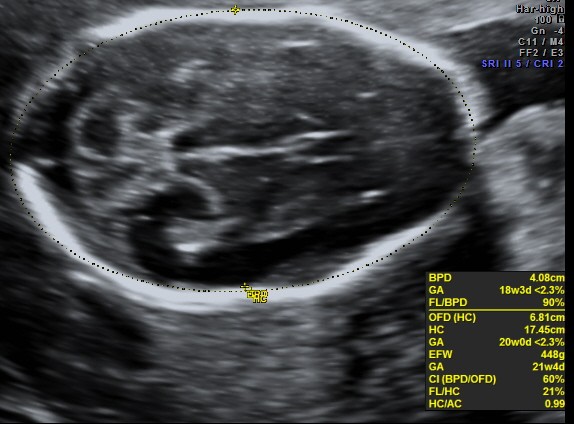

microcephaly (BPD &HC are less than <2.3 %tile )